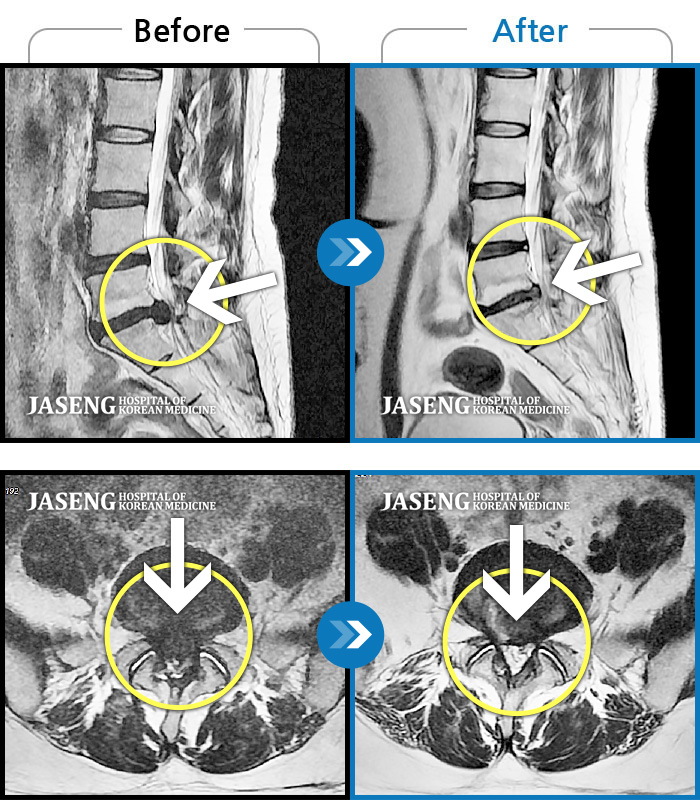

허리디스크

도움받은 사례

목동 · 고웅 원장

심한 허리 통증

촬영시기

2022.12.23 ~ 2024.12.04

2024.12.24